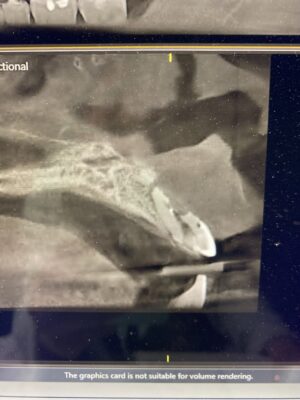

If you have time for another – how would you manage this case? 33yr old male with a chronic abscess and draining sinus tract from tooth 21 (or 9). External resorption on the middle to apical parts of the root were confirmed in CBCT. What type of bone grafting would need to be done / ie how do you repair the buccal plate? how long do you wait to graft after the initial extraction is done? Do you provide an essix as a temporary?

Here are his scans. Not sure if this bite is entirely accurate but there is no contact on the two centrals.

I typically wait 4mo. On a healthy patient when there was no real defect at the site. If I have to repair a missing buccal wall then it’s usually 5mo. Or so. Also, typically the easiest way to identify I difficult nerve is to start at the mental Foreman which is much easier to identify and then follow the nerve more posterior to approximate where it is.